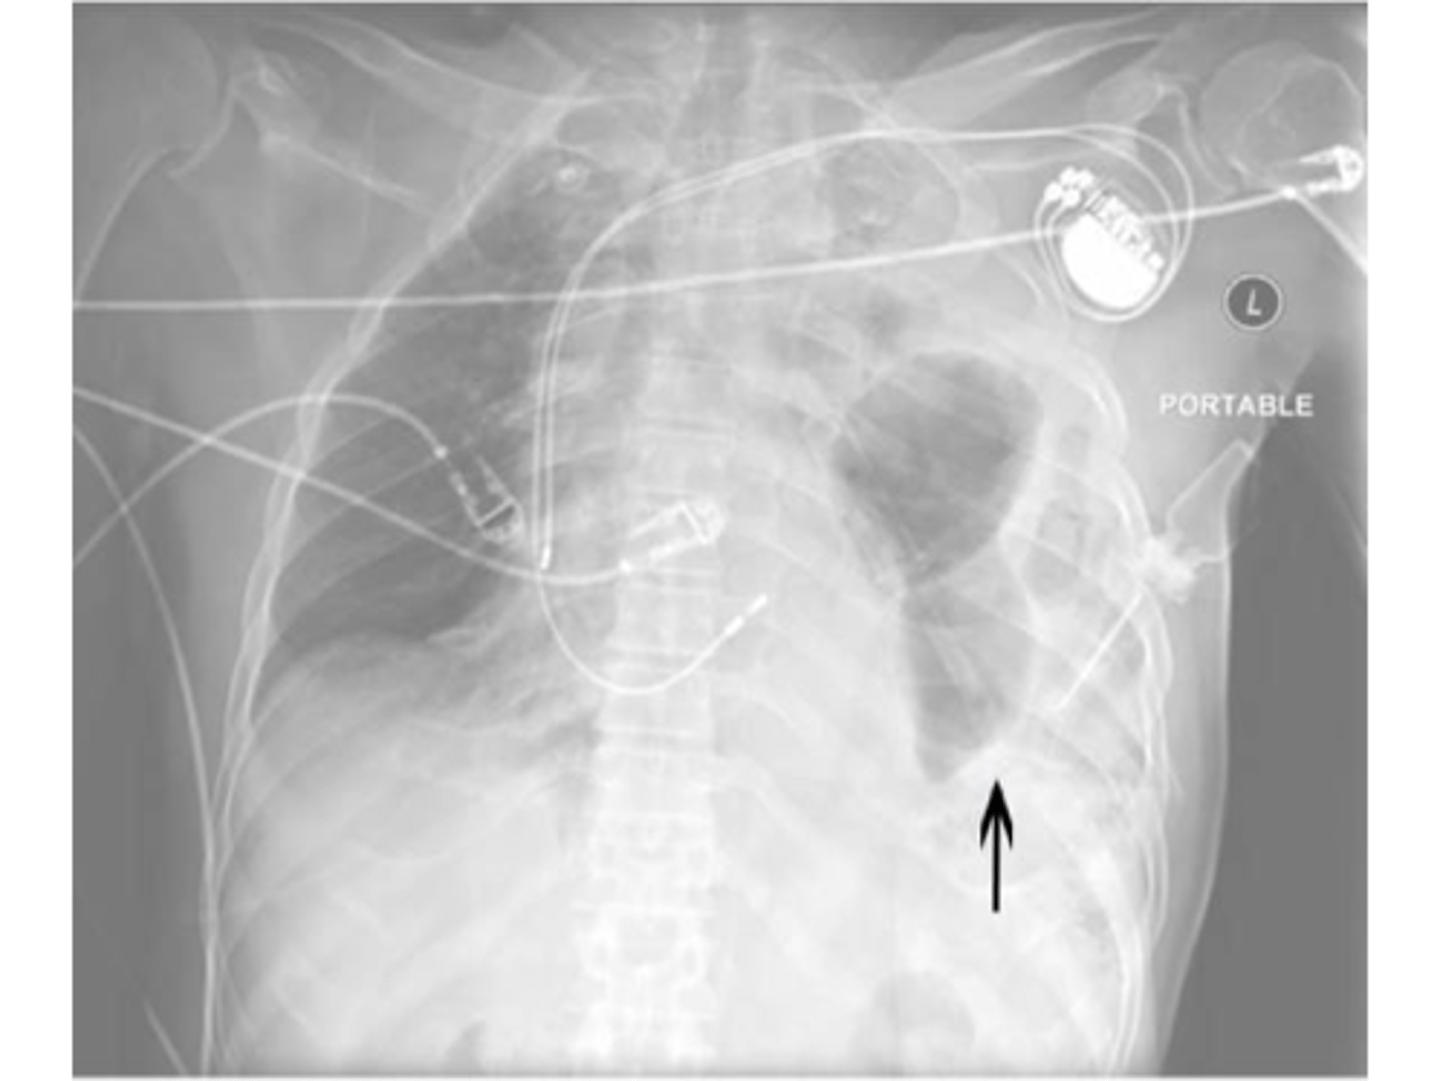

Pneumomediastinum (mediastinal emphysema)

knowt flashcard image